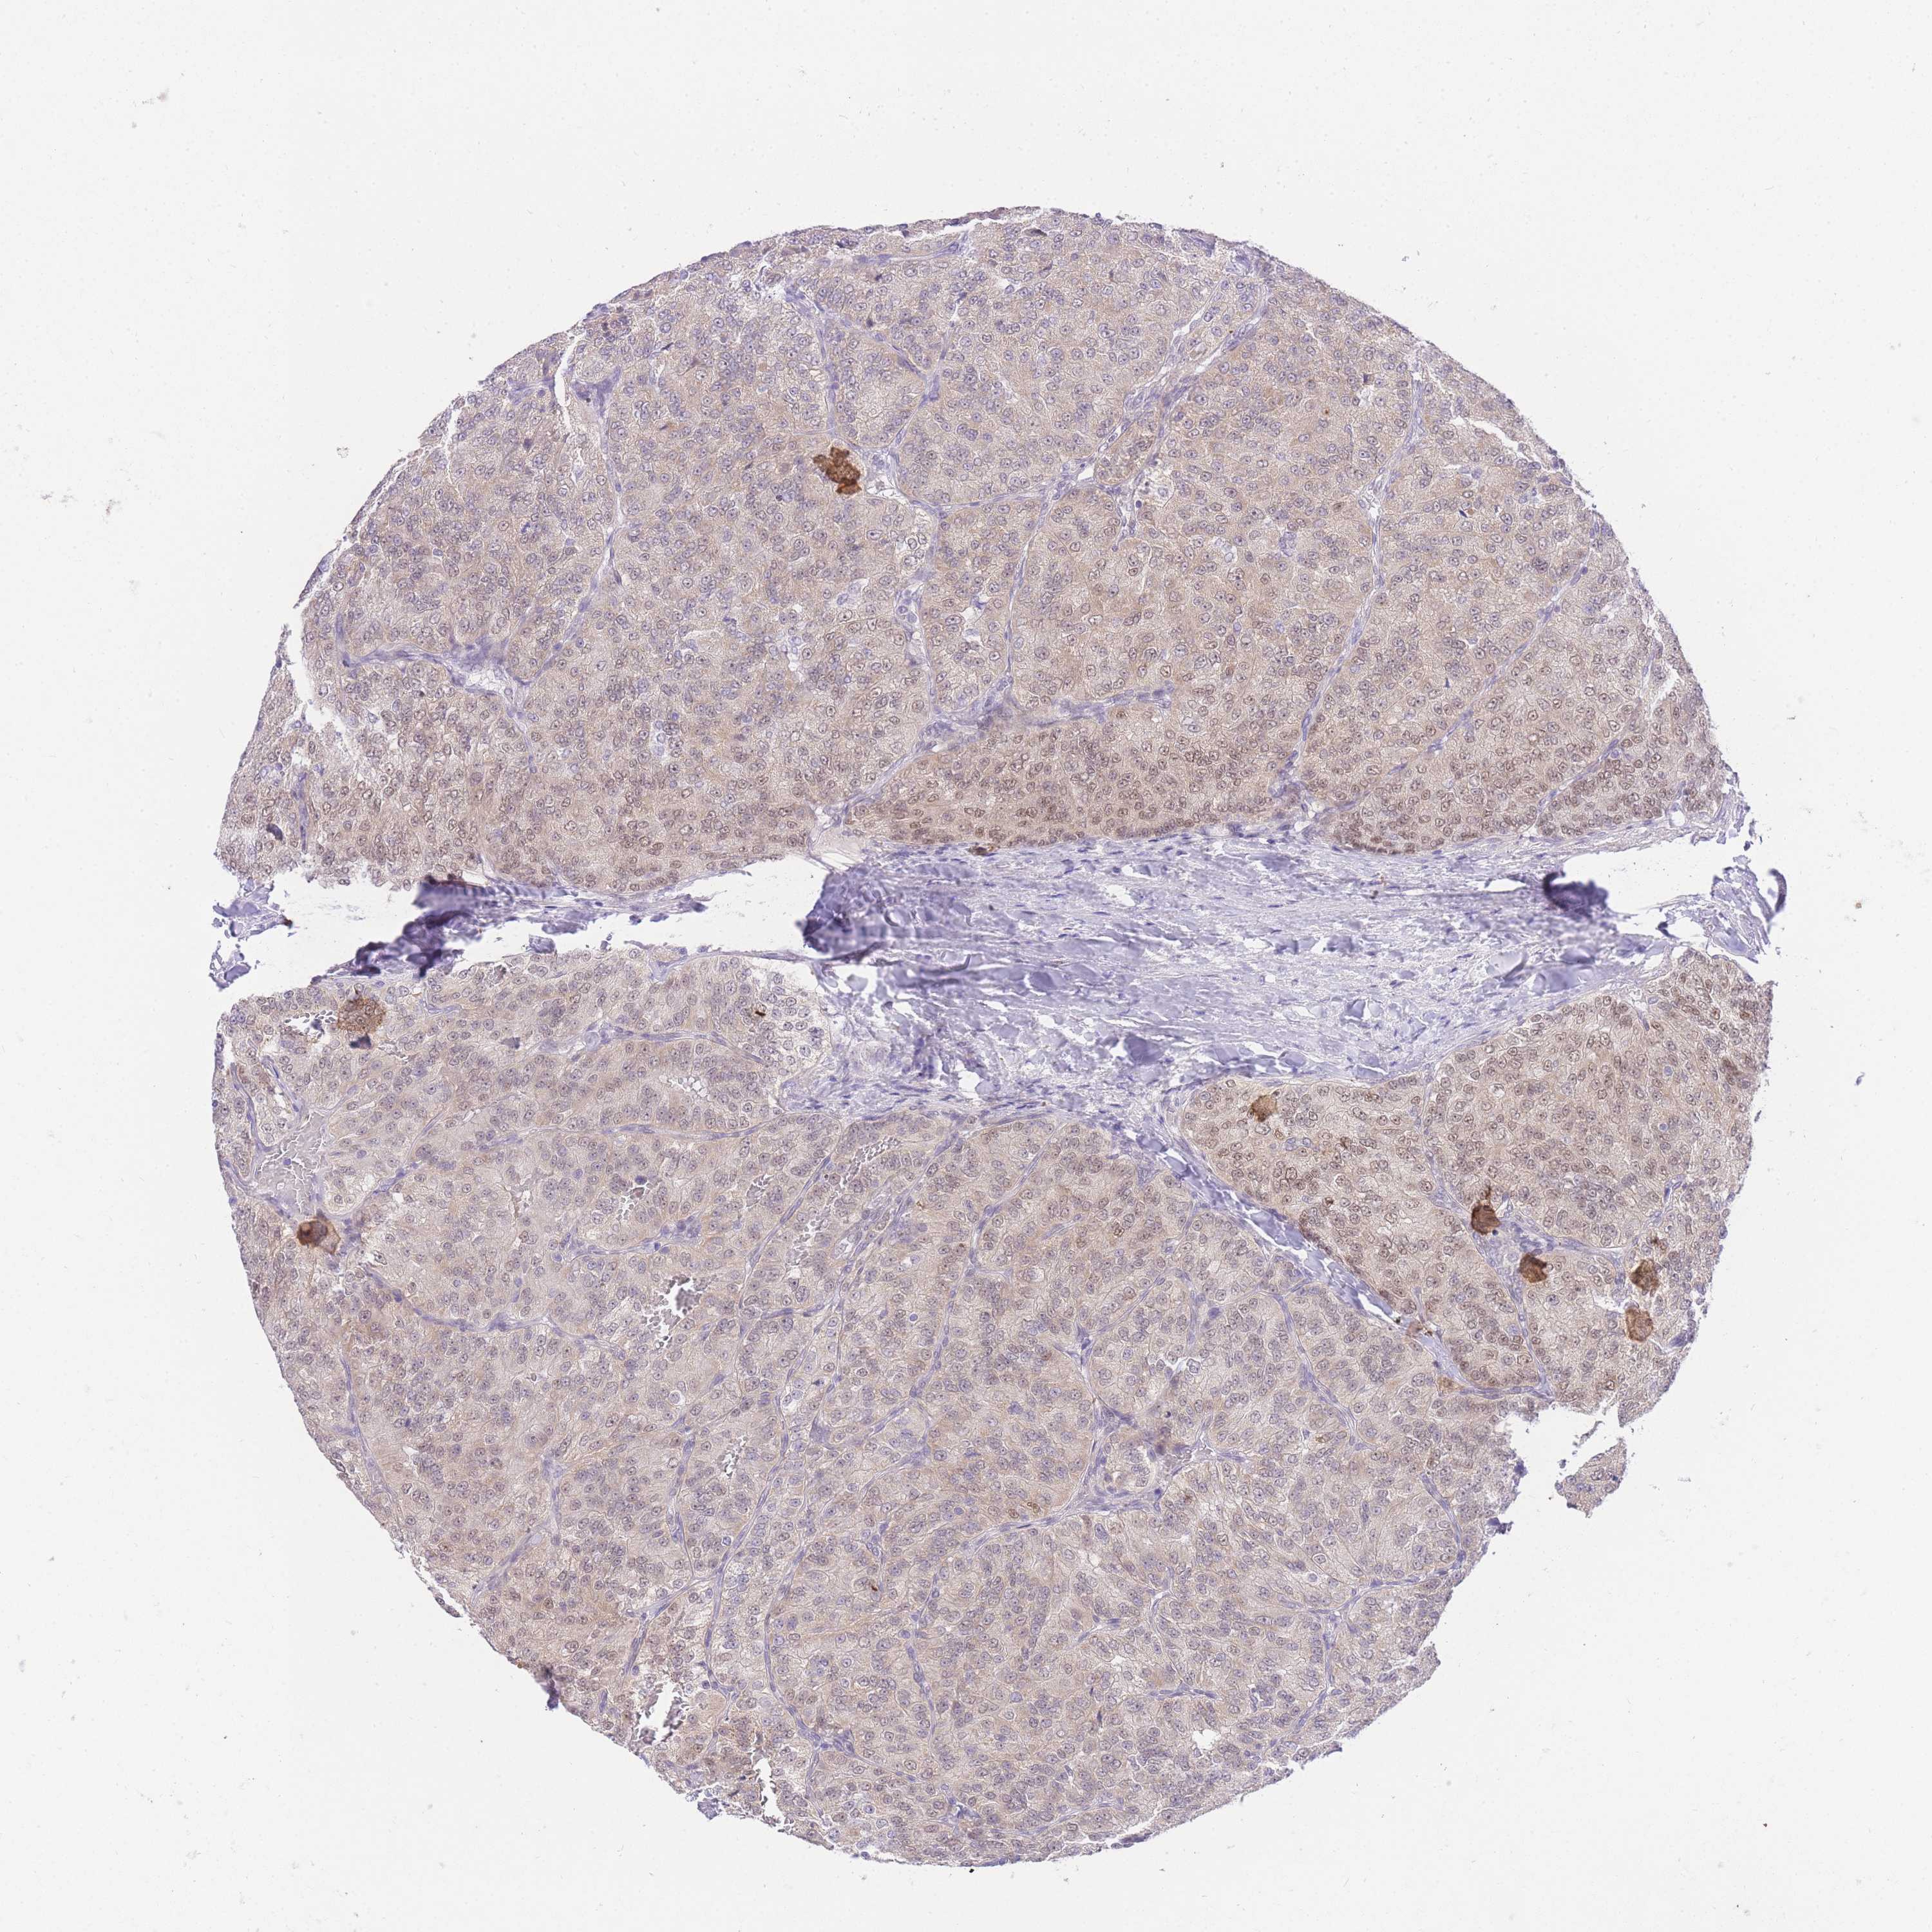

KICH TCGA KIRC TCGA KIRC VALIDATION KIRP TCGA PROTEIN RCC CPTAC PROTEIN EXPRESSION

KIDNEY RENAL CLEAR CELL CARCINOMA (VALIDATION) - Interactive survival scatter ploti

The Survival Scatter plot shows the clinical status (i.e. dead or alive) for all individuals in the patient cohort, based on the same data that underlies the corresponding Kaplan-Meier plots. Patients that are alive at last time for follow-up are shown in blue and patients who have died during the study are shown in red.

& Survival analysisi

UBXN7 is not prognostic in Kidney Renal Clear Cell Carcinoma (validation)

Best expression cut offi

: 10.65

Median expressioni

: N/A

P scorei

N/A

TCGA RNA samplesi

Average pTPM 9.7

Number of samples 100